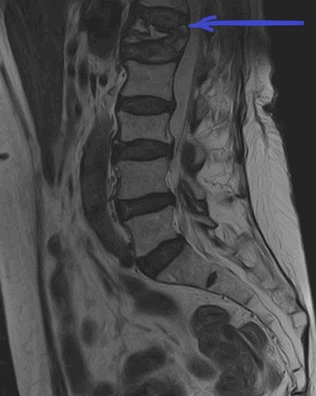

МРТ пояснично-крестцового отдела позвоночника. На Т2-ВИ в сагиттальной плоскости определяется компрессионный перелом L1 позвонка на фоне остеопороза.